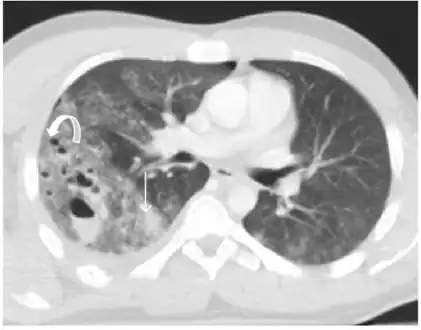

Pulmonary lacerations- Multiple focus of pulmonary lacerations can be depicted, some of them are filled with air, others filled with blood, and some filled with both, making an air-liquid level

Pulmonary laceration may not be visible using chest X-ray because an associated pulmonary contusion or hemorrhage may mask it.[1][9] As the lung contusion clears (usually within two to four days), lacerations begin to become visible on chest X-ray.[3] CT scanning is more sensitive and better at detecting pulmonary laceration than X-rays are,[1][5][12][15] and often reveals multiple lacerations in cases where chest X-ray showed only a contusion.[12] Before CT scanning was widely available, pulmonary laceration was considered unusual because it was not common to find with X-ray alone.[12] On a CT scan, pulmonary lacerations show up in a contused area of the lung,[9] typically appearing as cavities filled with air or fluid[16] that usually have a round or ovoid shape due to the lung's elasticity.[4]

Hematomas appear on chest radiographs as smooth masses that are round or ovoid in shape.[1] Like lacerations, hematomas may initially be hidden on X-ray by lung contusions, but they become more apparent as the contusion begins to heal.[1] Pneumatoceles have a similar shape to that of hematomas but have thin, smooth walls.[17] Lacerations may be filled completely with blood, completely with air, or partially with both.[4] Lacerations filled with both blood and air display a distinctive air-fluid level.[4] A single laceration may occur by itself, or many may be present, creating an appearance like Swiss cheese in the radiography of the lung.[4]